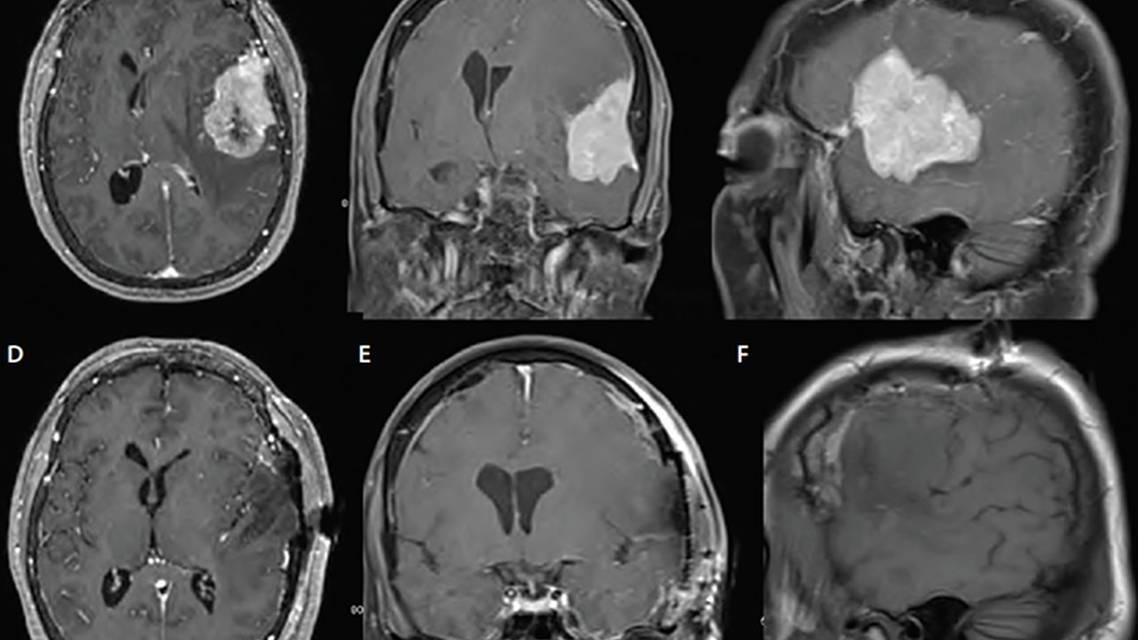

An Hispanic woman, age 52, presented with persistent dizziness and the inability to “bring out certain words.” She had been having difficulty speaking for a number of months. Recently, she began to notice some clumsiness in her right hand and occasional weakness in her right leg. Her neurologic examination showed severe expressive aphasia and mild right hemiparesis. Brain MRI showed a dural-based left frontotemporal convexity lesion measuring 5.7 cm x 3.2 cm x 5.1 cm, diving into the left Sylvian fissure (Figure 1).

Our patient underwent uneventful gross total resection of the lesion, which, during surgery, was confirmed to arise from the dura and invade overlaying bone, the latter of which was removed with margins. Lesion pathology was consistent with World Health Organization (WHO) grade II atypical meningioma (Figure 2). The patient’s weakness resolved and her aphasia improved. She has been referred for a clinical trial for higher-grade meningiomas and was randomized to observation. She will continue to be followed clinically and radiographically.